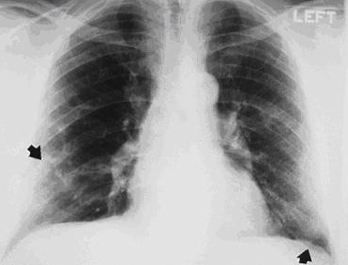

CXR demonstrating pleural thickening (indicated by arrows)

From the personal collection of Kenneth D. Rosenman, Michigan State University